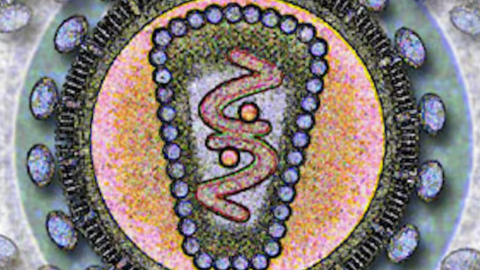

Para empezar, en 1981 apareció el SIDA, que se ha cobrado hasta ahora más de 50 millones de vidas. Todavía en la actualidad, cada año se infectan por VIH 1,5 millones de personas en el mundo.